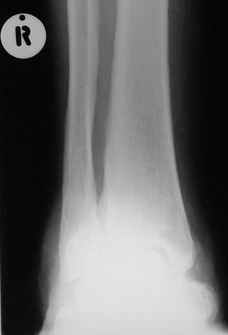

Отдельные случаи мелореостоза отличаются друг от друга по степени и форме склеротических участков; каждый случай

представляет свои неповторяемые особенности. В более тяжелых случаях поражения нижней конечности захвачена и

соответствующая половина таза, при локализации в верхней конечности - часть лопатки. Из парных костей поражается,

как правило, только одна: это большеберцовая или малоберцовая кость, лучевая или локтевая кость, но никогда не

обе кости одновременно. Мы наблюдали изолированные поражения не только периферических, но и ближе к туловищу

расположенных костей, например, бедра без вовлечения в процесс голени, или половины таза с соответствующей

половиной нижних поясничных позвонков и проксимальной части бедренной кости. Другими словами, в редких случаях

объем изменений совсем не возрастает по направлению к.периферии. В самых редких случаях в какой-то ничтожной

степени в процесс может быть вовлечен череп (часть нижней челюсти). Поражения ребер мы ни разу не наблюдали.

Измененный корковый слой, а также уплотненные эпифизы и мелкие губчатые кости приобретают плотность слоновой

кости. Корковый слой утолщается как в сторону костномозгового канала (эндостальная форма), в большей или меньшей

степени суживая его, так и наружу (периосталь-ная форма), возвышаясь над нормальным уровнем кости и увеличивая

этим ее наружный диаметр. Поверхность "наплывов" слегка волниста, с гребневидными возвышениями и углублениями, но

всегда резко конту-рируется. Склеротические полосы и ленты бывают чаще всего сплошными, но нередко они

прерывисты, расслоены. Иногда наблюдается некоторое удлинение костей и их небольшая дугообразная деформация, а

подчас и наоборот - очень незначительное укорочение. Это зависит, надо думать, от участия энхондрального хряща,

раздражения или торможения его функции. Костная ткань в соседстве со склеротическими полосами и островками

сохраняет нормальный рисунок или часто слегка поротична, так что граница между затемненными склеротическими

лентами и костным фоном очень резка. Иногда в мягких тканях таза или области плечевого пояса развиваются

неправильные шаровидные плотные костные массы, а при прогрессировании болезни подобные островки появляются и в

окружности суставов, которые сами по себе особых изменений не представляют. Патологические переломы при

мелореостозе не описаны. Мы также по собственному опыту и по литературным данным не знаем озлокачествления при

мелореостозе. Течение болезни вообще вполне доброкачественное и общее предсказание благоприятное.